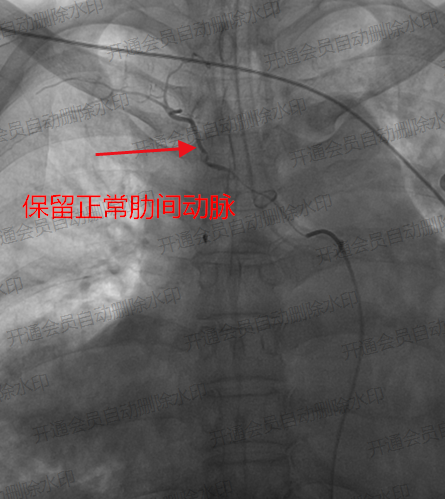

▲保留正常肋间动脉供血